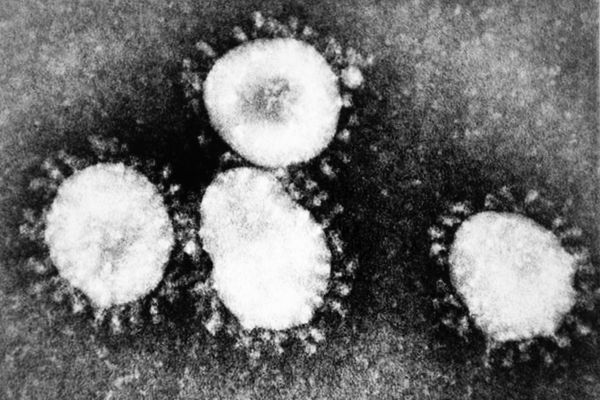

Italy entered a lookdown. Today I see the images taken forcibly closed in the house.

Italy entered a lookdown. Today I see the images taken forcibly closed in the house. I was trying to transfer my feelings into photography. Looking at them I recognize my mood at the time, the tension, the disbelief of what I was experiencing.